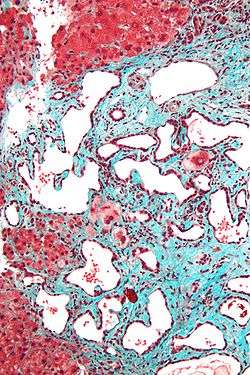

Micrograph of a bile duct hamartoma. Trichrome stain.

Low magnification micrograph of a bile duct hamartoma. Trichrome stain.